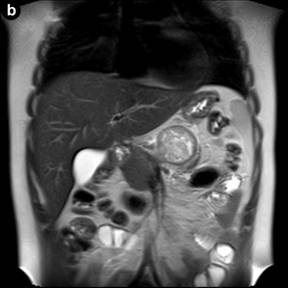

Figure 3. Axial fat-supressed (a.) and coronal (b.) T2-weighted MR images show a well-marginated lesion, heterogeneously hyperintense, in the body/tail of the pancreas, with a hypointense fibrous pseudocapsule. c. On an axial unenhanced fat-suppressed T1-weighted MR image the fibrous pseudocapsule is also hypointense (white arrow) and there is an internal peripheral high signal intensity rim (black arrow), a finding consistent with hemorrhage. |